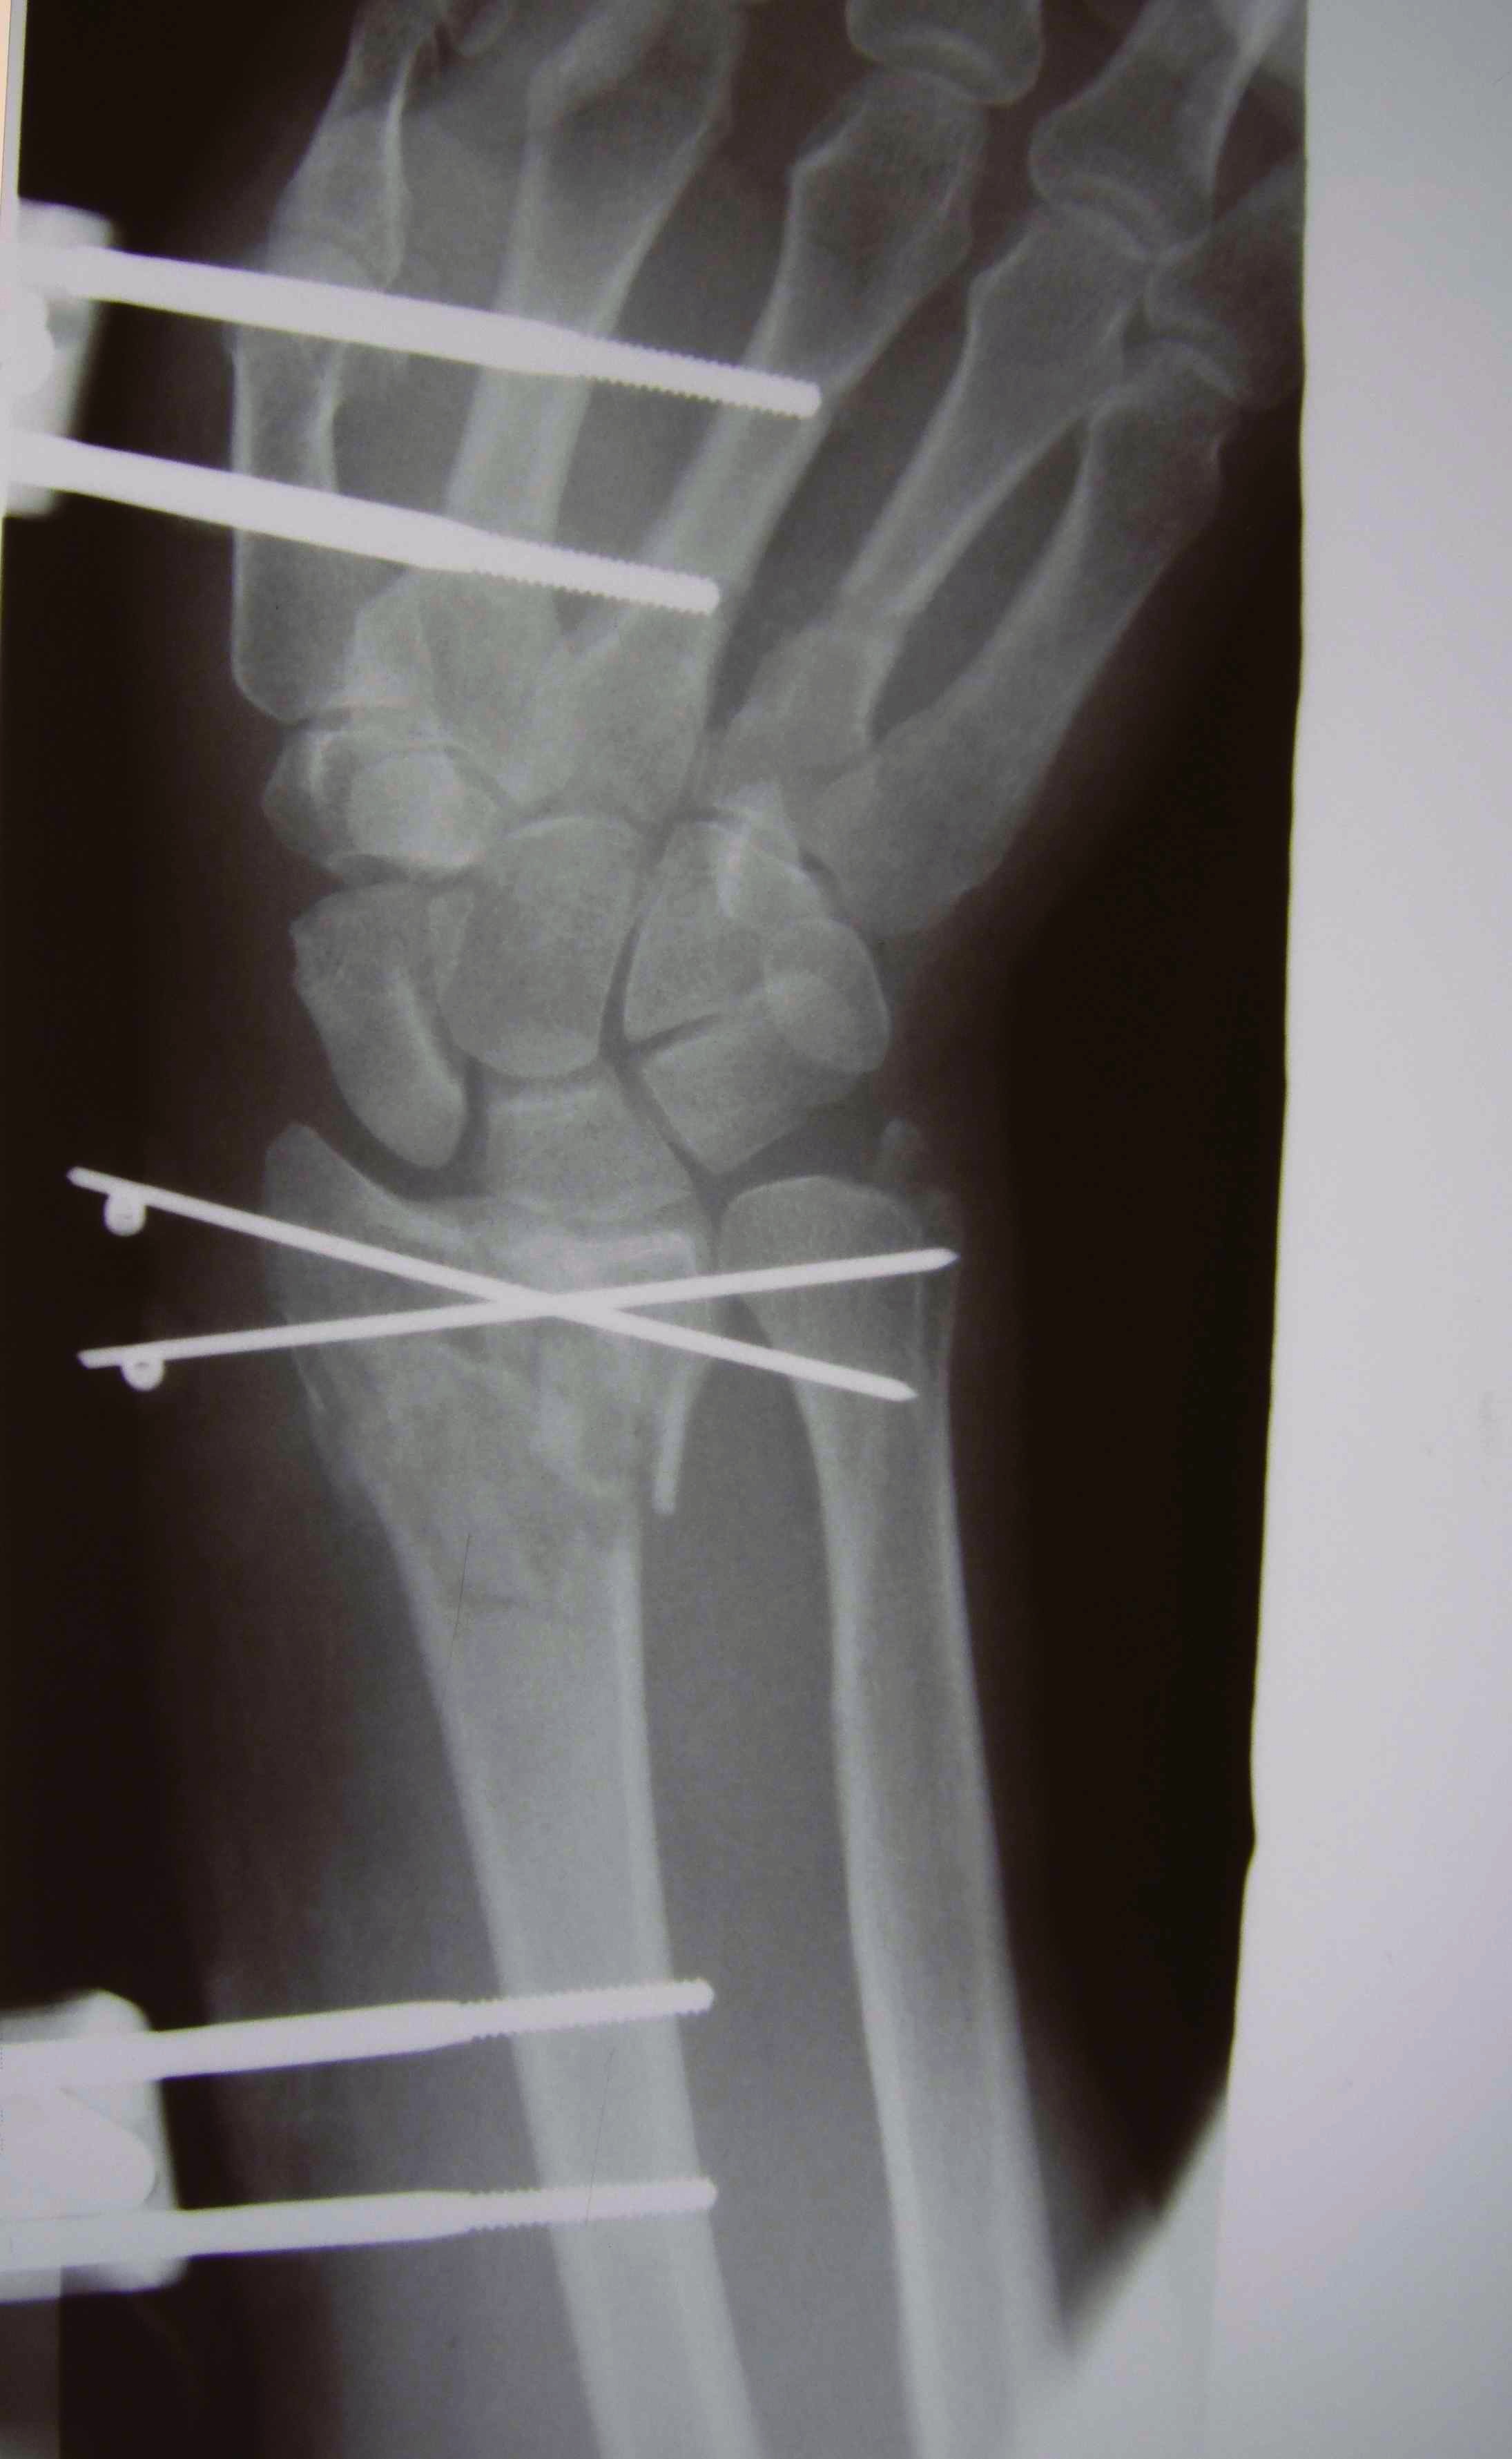

Dr shortDR short

Distal radius fracture with shortening and dorsal tilt

Distal Radius Fracture DRUJ incongruentDRUJ FractureDRUJ Fracture CT

Sigmoid notch disruption and DRUJ instability